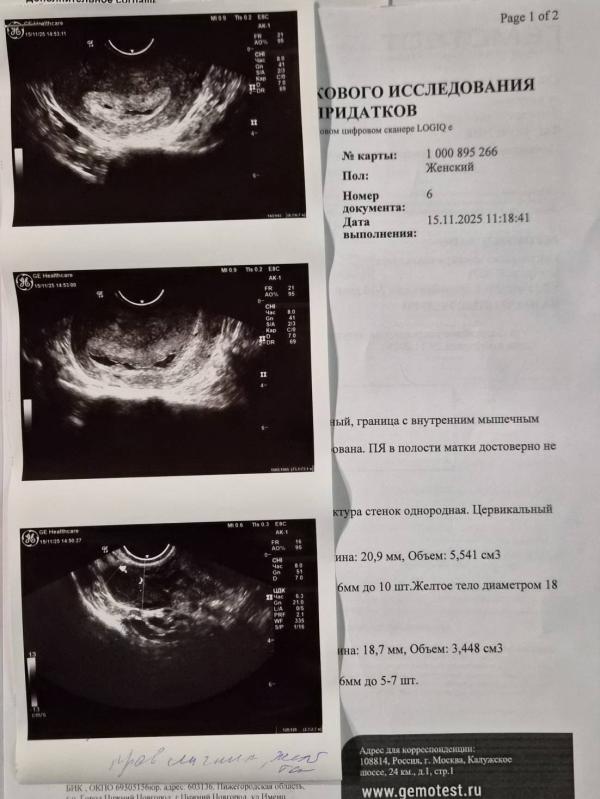

@em.galtsova если эндометрий больше 12 мм,то это либо потология, либо беременность. Но судя то что есть // это пузожитель поселился👌

Пока просто наблюдать при хгч от 1500 уже точно найдется ПЯ на повторном узи

Ну если тест от 10, уже должно быть. У меня 4,6 все видно было уже. Тест был чуть ярче

У вас еще полоски не сравнялись, хгч видимо не сильно большой, поэтому не видно.

@em.galtsova, а у вас какой день цикла? У нас с вами срок рядышком совсем, у меня 6 и 3 дня, тест показал 24.10, вчера была на узи и уже включали сердцебиение. Возможно тогда у вас поздняя овуляция.